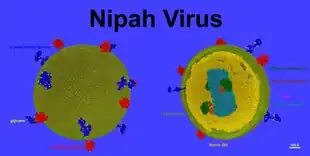

Das Nipah-Virus (NiV, auch NIPV, Spezies Henipavirus nipahense) ist ein Virus aus der Familie Paramyxoviridae,[3][4] das beim Menschen eine häufig tödlich verlaufende Gehirnentzündung (Enzephalitis) auslösen kann. Das Nipah-Virus tritt insbesondere in Südasien und Südostasien auf und kann durch Kontakt mit Körperflüssigkeiten und -ausscheidungen infizierter Tiere, Menschen oder Reservoirwirte oder dem Verzehr von kontaminierten Lebensmitteln übertragen werden. Reservoirwirte sind fruchtfressende Flughunde der Gattung Pteropus, die in Süd- und Südostasien sowie auf Madagaskar vorkommen. Diese Flughunde scheiden das Virus z. B. über Urin und Speichel aus und übertragen es in der Regel auf andere Tiere (insbesondere Schweine), die es auf den Menschen weiterübertragen.[5]

Systematik

Das Nipah-Virus bildet zusammen mit dem eng verwandten Hendra-Virus die Gattung Henipavirus in der Familie der Paramyxoviridae. Es wurde erstmals 1999 im Zuge der Untersuchungen des Ausbruchs in Malaysia und Singapur charakterisiert.[6] Das isolierte Virus war morphologisch dem kurz zuvor in Australien entdeckten Hendra-Virus sehr ähnlich, jedoch im Krankheitsverlauf und seiner Antigenität doch von diesem verschieden. Es wurde daher vor einer endgültigen Benennung zunächst als Hendra-like Virus bezeichnet. Das neue Virus erhielt seinen taxonomischen Namen in Anlehnung an den kleinen Ort Kampung Teluk Nipah auf der malayischen Insel Pangkor, wo die Epidemie von 1998 besonders hohe Infektionszahlen aufwies und das Virus aus einem von dort stammenden Patienten isoliert wurde.